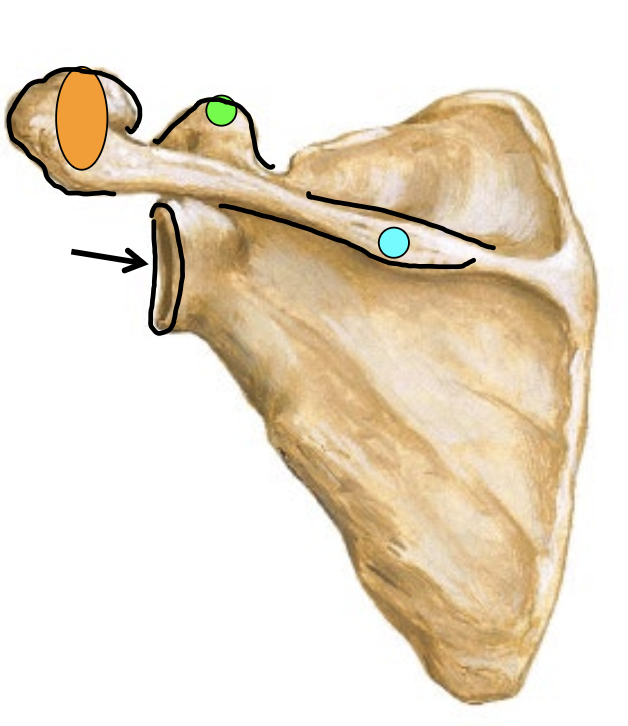

What is the arrow locating in this image?

Glenoid Fossa

What is the blue dot locating in this image?

Spine of scapula

What is the orange dot locating in this image?

Acromion process

What is the green dot locating in this image?

Caracoid process